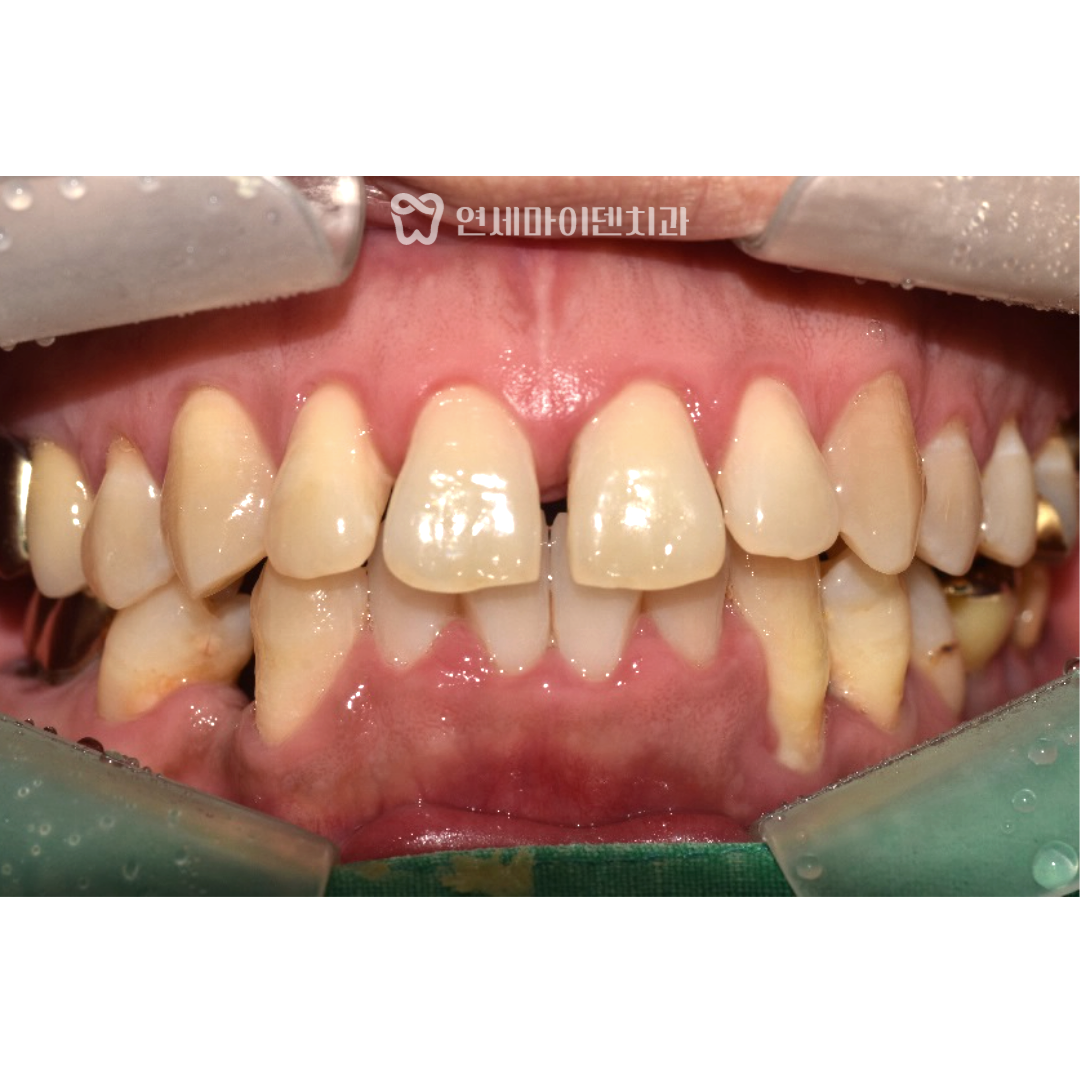

치열은 가지런하게 정리되었고, 처음 진단 때와 비교하면

눈에 띄게 달라진 모습을 확인할 수 있습니다.

특히 처음에 걱정했던 잇몸 염증도 치주치료와 병행해서

치료 과정 중 잇몸이 더 내려가거나 건강이 악화되는 일 없이

치료 마무리까지 잘 유지되었습니다.